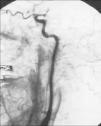

La ausencia de relleno de contraste de la circulación arterial de ambas carótidas internas y del sistema vertebrobasilar es un criterio absoluto en el diagnóstico de muerte encefálica. Ahora bien, los hallazgos angiográficos pueden ser de varios tipos9. Raramente puede haber un progresivo afilamiento del contraste hasta que se detiene completamente en la porción cervical de la carótida interna a distancia variable (fig. 1), pero lo habitual es que el contraste se detenga abruptamente a nivel de la base craneal o en el sifón carotídeo, cerca de la clinoides anterior o posterior, con o sin visualización de la arteria oftálmica (fig. 2). En casos muy raros puede existir un llenado tardío tenue de la porción supraclinoidea de la carótida interna y de la porción más proximal de la cerebral media y, más raramente, de la cerebral anterior. El contraste se detiene normalmente de forma simétrica en ambas circulaciones carotídeas (fig. 3), aunque puede haber cierta asimetría. En todos los casos se obtiene un llenado completo e incluso precoz de las ramas de la arteria carótida externa bilateralmente. Nunca se observa llenado en fase venosa. A nivel del sistema vertebrobasilar la detención del contraste se produce en la entrada de la cavidad craneal, a nivel de la unión occipitovertebral. De modo ocasional puede rellenarse de forma filiforme la porción más proximal de la arteria basilar, rellenándose retrógradamente la arteria vertebral del otro lado. Kricheff et al2 estudiaron el patrón angiográfico de 20 pacientes y lo dividieron en cinco grupos. El grupo I consistía en una ausencia completa de relleno de las arterias intracraneales (10 casos), el grupo II con estasis prolongada de las arterias basales (3 casos), el grupo III con fenómenos de reflujo y shunts (4 casos), el grupo IV con conservación solamente de la vasculatura de fosa posterior (2 casos) y finalmente el grupo V con 1 solo caso con extravasación perivascular del contraste en la distribución de la arteria cerebral posterior durante la inyección en la arteria carótida interna.

Fig. 1. Angiografía digital selectiva de carótida común en proyección lateral. El contraste en la carótida interna se va afilando progresivamente en su recorrido cervical desde la bifurcación hasta que se detiene completamente al llegar a la base craneal, mientras que la carótida externa se visualiza con normalidad.

Fig. 2. Angiografía digital selectiva lateral de carótida que muestra una abrupta detención del contraste en porción supraclinoidea de carótida interna.